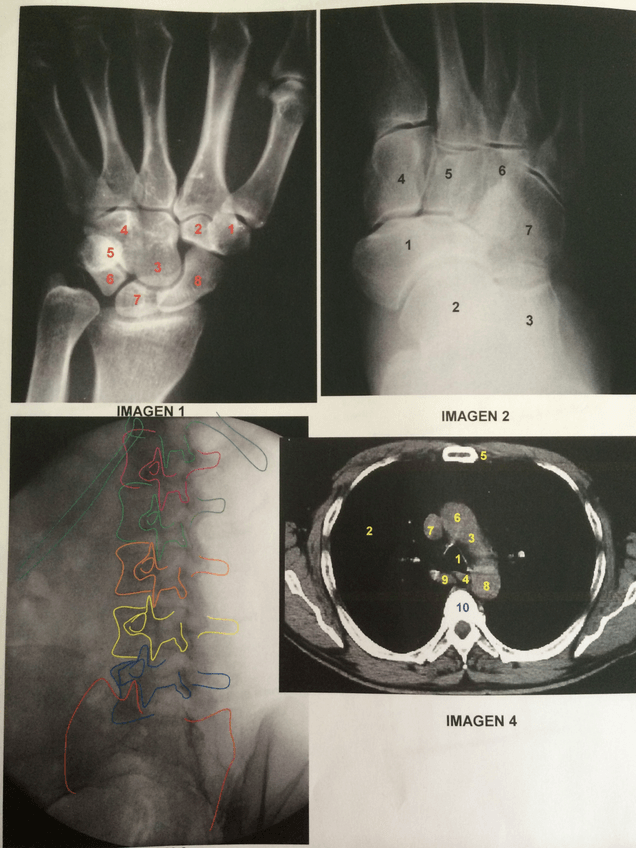

PRACTICA-3-TECNICA-ANATOMIA-MS.pdf